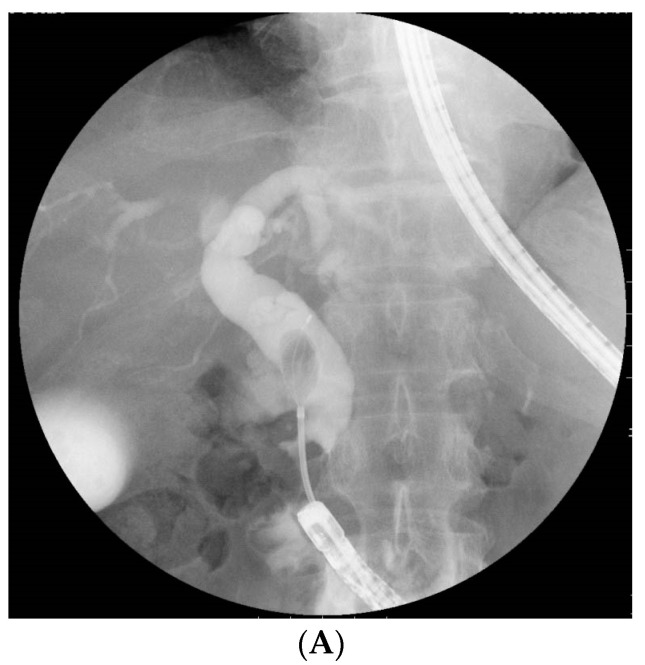

The primary outcome of this study was to reveal the factors affecting complete stone extraction using variables associated with both patient characteristics and procedural contents. The patient-related factors were age, sexuality, the American Society of Anesthesiologists physical status (ASA-PS) classification, diameter of the largest CBD, size of the largest CBD stone, number of stones, and time from RYG to BE-ERCP. Furthermore, the procedure-related factors were initial BE-ERCP, EST/precutting or EPBD/EPLBD, and retroflex position, which was able to provide a better view of the papilla with a J-turn form of the scope at the inferior duodenal angle (IDA) [ref. 20] (Figure 1). The secondary outcomes were the technical success rates of initial BE-ERCP, including the rate of reaching the papilla, rate of biliary cannulation, and rate of biliary intervention, such as complete stone extraction and biliary stent placement, as well as adverse events. Complete stone extraction was defined as no detection of residual stones by a cholangiogram. The time to reach the papilla was the duration from the scope insertion to when the papilla was reached. The time to biliary cannulation was the duration from when the papilla was reached to the achievement of biliary cannulation. The total procedural time was defined as the time from scope insertion until withdrawal. Adverse events were defined according to the ASGE guidelines [ref. 34].

In addition, a retroflex position was identified as a positive factor affecting complete stone extraction. As mentioned above, this position was reported to be useful for successful biliary cannulation in RYG patients [ref. 20,ref. 22]. The retroflex position can be obtained by advancing the endoscope without releasing the looped scope and forming a J-turn at the IDA. Thereby, a coaxial relationship between the devices and distal CBD and maintaining a proper distance from the tip of the scope to the papilla of Vater with a better view of the papilla can thus be obtained. Such a situation can facilitate stones to be removed along the axis of the CBD. In the present study, in a sub-analysis of the difficult-to-manage cohorts—i.e., those with a large CBD diameter (≥14 mm) or stone size (≥10 mm)—the retroflex position was also a significant factor affecting successful complete stone extraction. In fact, we experienced several cases where stone extraction could not be completed initially in the non-retroflex position, whereas the retroflex position allowed complete stone extraction to be easily performed in the second session, as shown in Figure 1. Taken together, these findings suggest that the retroflex position may be recommended for complete stone extraction as well as successful biliary cannulation in RYG patients. However, this technique should be performed carefully due to the risk of perforation at the IDA.